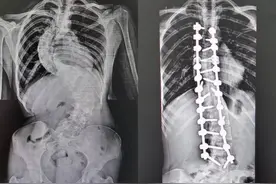

长沙晚报掌上长沙7月29日讯(全媒体记者 傅容容 通讯员 章茹)“9月开学,我可以自信地回到校园了!”今日,在湖南省第二人民医院脊柱外科,来自溆浦县的16岁女生小琳(化名)非常开心。被脊柱侧弯困扰多年的她,终于挺直了腰杆,“长高”6厘米。

暑假期间,来自溆浦县的小琳(化名)同学在湖南省第二人民医院“长高”了6厘米。今年16岁的小琳在4年前因为腰背部反复疼痛,在当地确诊为脊柱侧弯畸形。由于家庭条件限制,加上学业紧张,一直没有进行系统的治疗。疾病给小琳的生活蒙上了一层阴霾。

来源:【华声在线】华声在线7月30日讯(全媒体记者 李琪 通讯员 章茹 黄艳 张警盈 曾星怡)“还有一个月开学,我可以自信地回到校园啦!”7月30日,湖南省第二人民医院脊柱外科,来自怀化溆浦县的16岁女生罗小琳(化名)开心地说道。